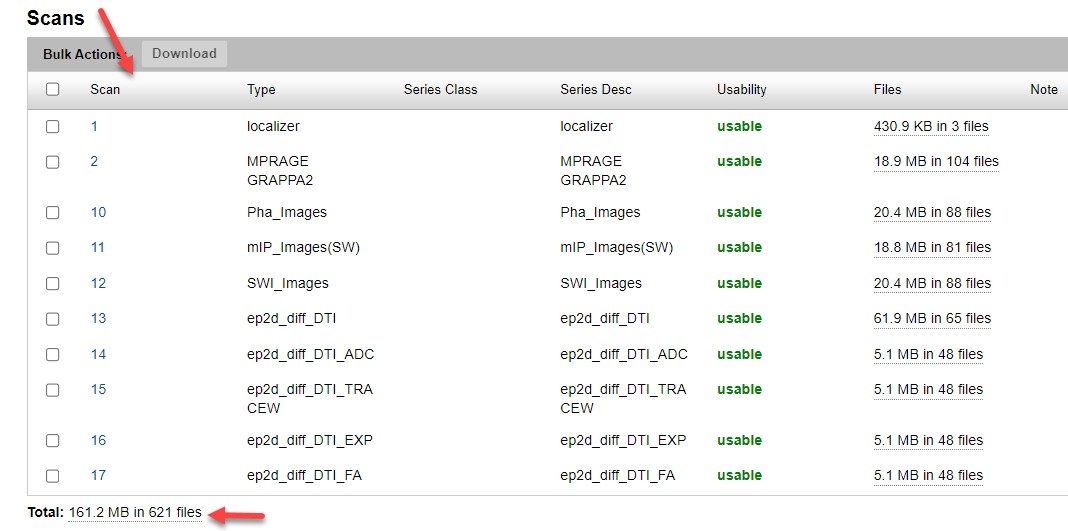

Confirm:

- All expected series are present

- Total file counts are correct

Upload process complete.